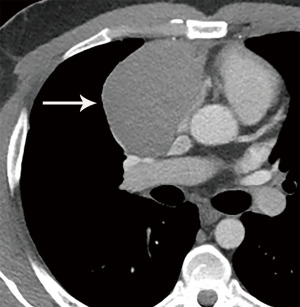

Computed tomography (CT) with contrast is the imaging modality of choice to evaluate thymic tumors due to its high spatial and temporal resolution, ease of access, and convenience. CT can reliably discern location, size/shape, morphology, margins, density, enhancement, and relationship to, or invasion of, adjacent structures (4) (Figure 2). Overall, CT is equal or superior to magnetic resonance imaging (MRI) in the evaluation of mediastinal masses with the caveat that MRI better evaluates thymic cysts or cystic components of tumors (5) (Figure 3).

Thymoma typically presents as a smooth or lobular mass involving one lobe of the thymus, although bilateral involvement can occur (39). Most thymomas demonstrate homogeneous enhancement, although, approximately one third can be heterogeneous due to areas of hemorrhage, necrosis, cystic change, or calcification (1) (Figures 8,9). Imaging characteristics can vary according to WHO histological classification, with vascular invasion and pleural/pericardial involvement more common with more aggressive histology (Figure 2). The thymomas with the more aggressive histologies tend to be larger, more lobular or irregular, have cystic or necrotic change, areas of calcification, or evidence of infiltration into surrounding fat (40-42) (Figure 10).

The role of FDG PET/CT in thymoma imaging is limited. Given the presence of FDG uptake in the normal and hyperplastic thymus, especially in younger adults and children, false-positive results can occur. In fact, physiologic uptake has been reported in 28% of patients under 40 years of age and up to 73% in children less than 13 years of age (44). PET/CT has not been shown to differentiate different WHO histological classifications of thymic tumors, although the more aggressive histologies tend towards higher FDG uptake (45,46) (Figures 2,3). Indium111 octreotide nuclear medicine scans have now been replaced by 68Ga-labeled somatostatin analogues because 68Ga-labeled somatostatin analogues, such as 68Ga-DOTATATE, are used for PET/CT, and thus provide better resolution.

Thymic carcinoma and thymic neuroendocrine tumors have similar imaging characteristics which may often overlap with the more aggressive histologies of thymoma, such as B3 thymoma. Thymic carcinomas and neuroendocrine tumors commonly present as large prevascular masses with irregular or poorly marginated borders, areas of necrosis or cystic change, and hemorrhage. Compared with thymomas, there is a greater incidence of local invasion (1) (Figures 2,11). Pleural or pericardial nodules, pleural effusion, and distant metastasis are more commonly seen with thymic carcinoma or thymic neuroendocrine tumor than thymoma (Figure 12). More aggressive thymic epithelial tumors can invade or compress the SVC resulting in SVC syndrome. This is a clinical syndrome marked by swelling of the neck, face, and upper extremities, with associated cough, headache, and shortness of breath. Pleural metastatic disease, which is more common in thymic carcinoma and thymic neuroendocrine carcinoma, generally consists of small enhancing pleural nodules or areas of enhancing pleural thickening. These are generally adequately assessed with thin-slice contrast-enhanced CT, although, contrast-enhanced MRI and PET/CT can be of additional benefit in questionable cases.